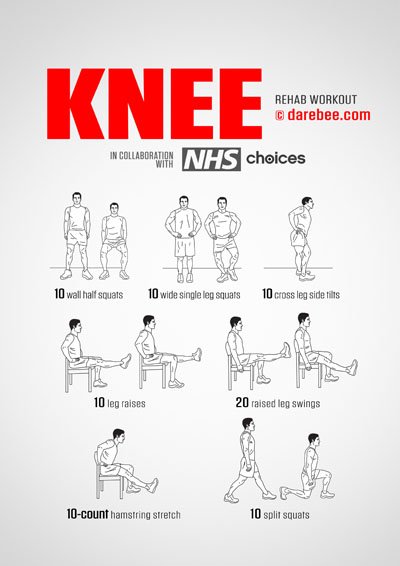

Knee rehabilitation after that requires gentle extensions and retractions of the knee while lying on your back to take the pressure off it and help increase flexibility and then knee strengthening exercises. Strong knees require strong muscles. There are four specific muscle groups that help stabilize the knee joint.

Knee Joint Strengthening Exercises

If the muscles that support the knee joint are naturally strong then there is a lot less pressure being applied on it by dynamic movements and even wear and tear is reduced. The exercises below help strengthen the relative muscle groups and, in addition, also work the tendons and ligaments of the knee helping to keep them supple. This maintains the knee’s range of motion.

Rehabilitating the knee requires constant work on all these muscle groups on an ever-increasing rep count. It may be necessary to also increase the frequency of the workout.

Workouts for the Knees